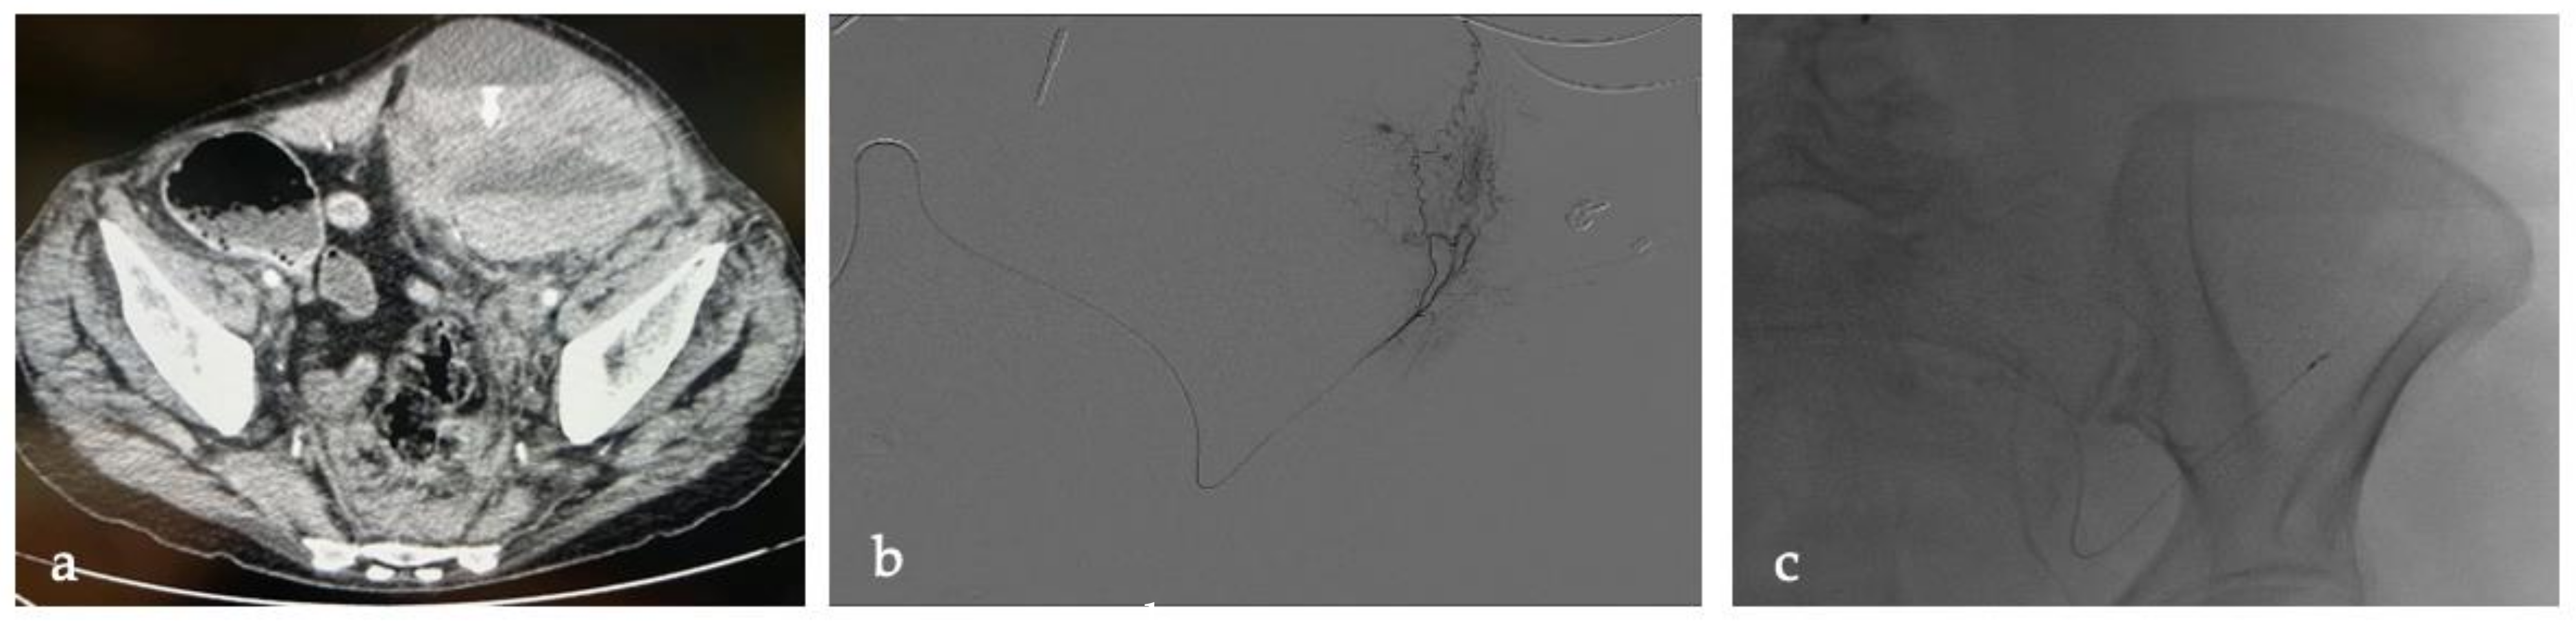

Figure 2.

LB, a 76-year-old woman under anticoagulant therapy (unfractionated heparin), developed a type 3 intramuscular hematoma in the left psoas muscle. (a) CT scan documented an intramuscular hematoma in the left psoas muscle. (b) DSA during selective catheterization of the left deep circumflex iliac artery confirmed active bleeding. (c) Microcatheter and proximal coiling in the deep circumflex iliac artery. Arteriographic control (not shown) confirmed complete exclusion of the bleeding segment and thus no contrast extravasation.